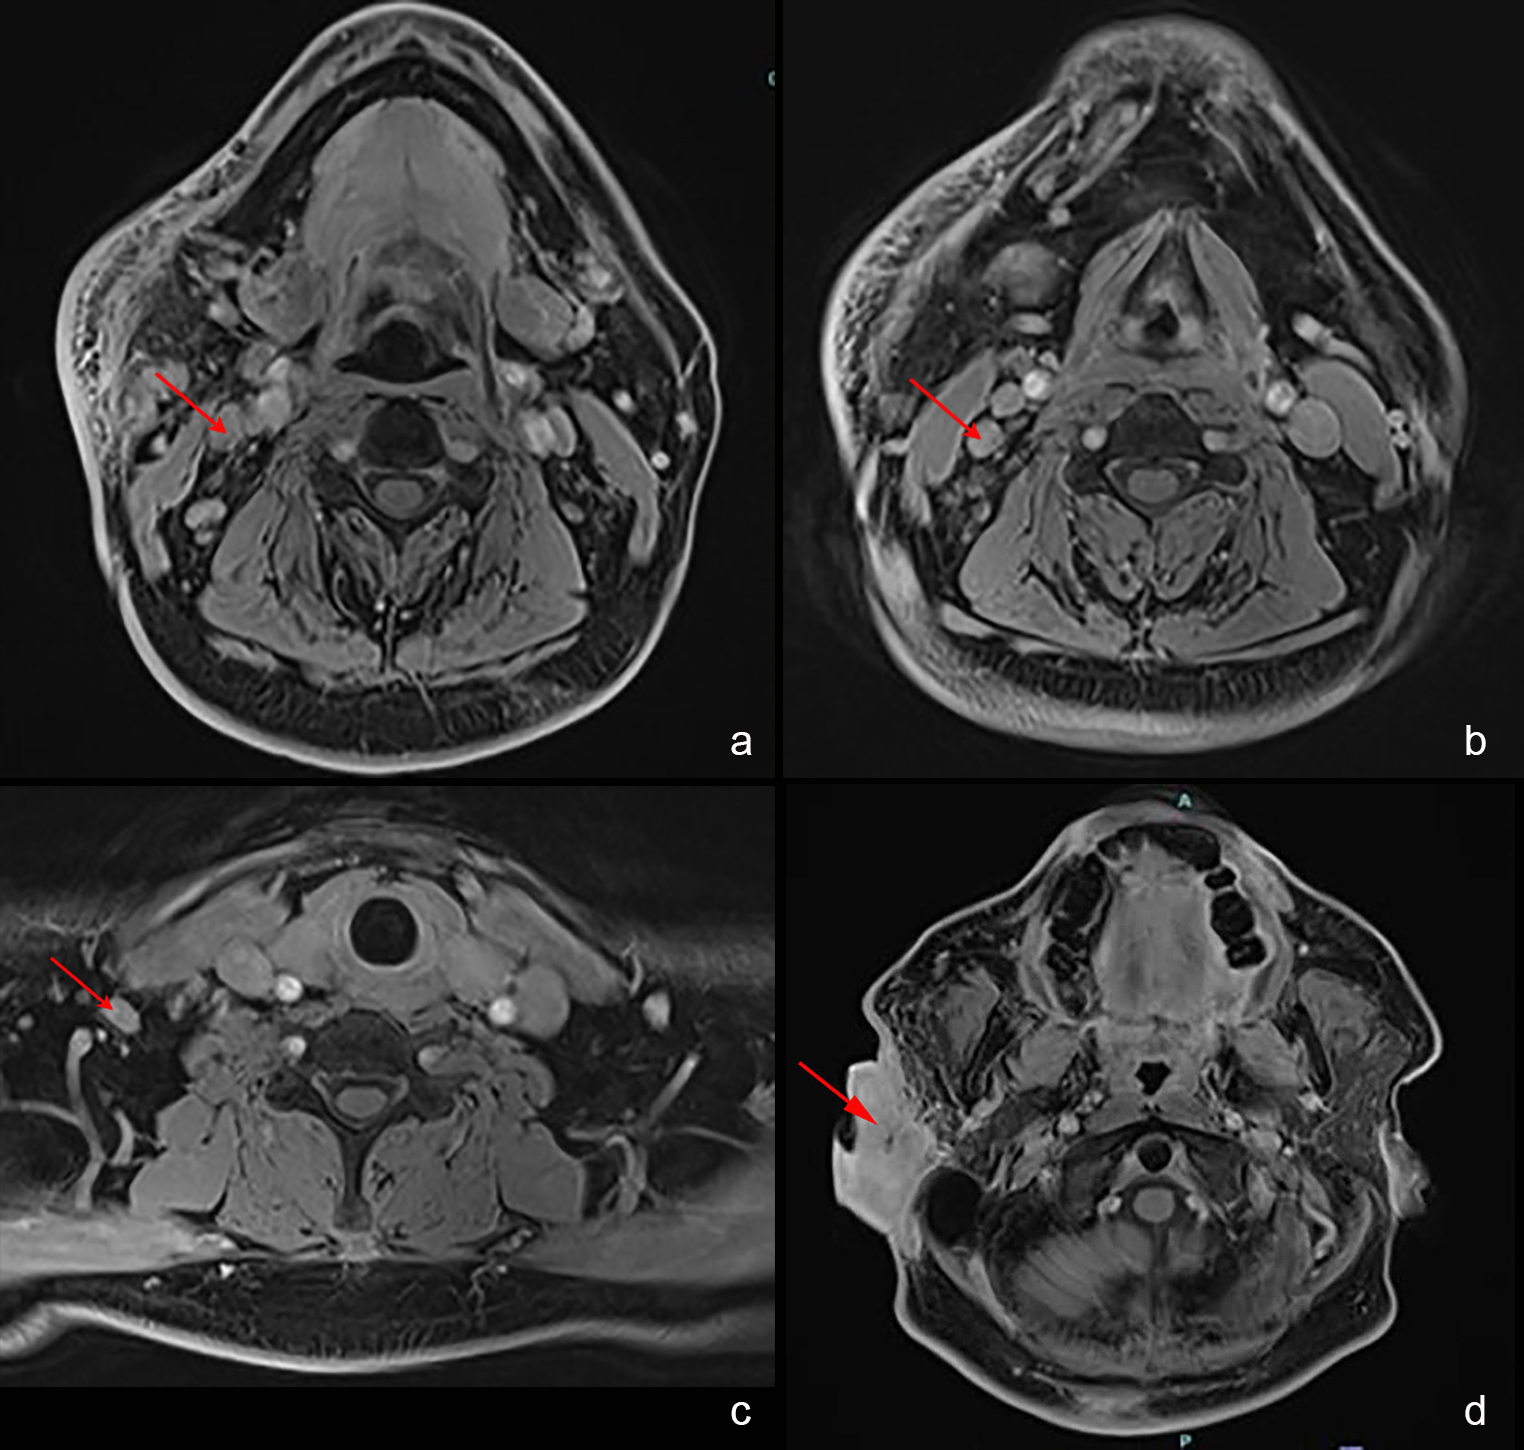

Kimura disease is a rare, chronic inflammatory condition predominantly affecting young adults, particularly those of Asian descent. It presents with subcutaneous nodules and regional lymphadenopathy, and while benign, it can cause significant disfigurement and recurrent issues. A 56-year-old male of Chinese descent with a history of Kimura disease presented with a recurrent mass in the right infraauricular area, initially diagnosed in 1987. Despite surgical resections and extended steroid therapy, disease recurrence persisted. The patient then underwent radiotherapy targeting the right cheek and mandible. He experienced excellent disease control for 12 years. However, in 2022, the patient experienced a relapse. Given the recurrence and prior response to radiotherapy, re-irradiation was considered but reserved as a last option due to potential risks. Instead, triamcinolone acetonide injections were administered, resulting in significant symptom improvement and control of the lesion. Management of Kimura disease remains challenging due to high recurrence rates. This case highlights the difficulties in managing recurrent Kimura disease after radiation and demonstrates the effectiveness of intralesional steroid therapy as an alternative treatment option.